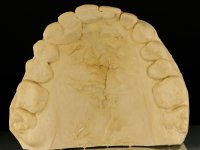

After the root canal treatment of tooth 11, dental impressions were taken to do a fixed provisional (reinforced) acrylic prosthesis. The provisional bridge included an acrylic component with a gum-shade color, to evaluate the integration of the treatment plan, in relation to function and esthetics. The preparation of teeth 14 and 13 were minimal invasive, with supra-gingival finishing lines, preserving enamel at its uttermost. Tooth 11 was prepared in a conventional way, with an intra-sulcular margin. The provisional bridge was rebased intra-oral with an autopolymerized acrylic. After 4 weeks, a dental impression with a double mixture technique was done. In the dental lab, CAD-CAM technology was used to produce a zirconia framework. In the provisional bridge, it was noted by the patient, and by ourselves, the need for symmetry in the dimensions and shape of the teeth, in relation to their homologues of the 2nd quadrant. Accordingly, a mirror effect was selected in the CAD design of the framework, to mimic in the prosthetic structure the dimensions and shape of the homologous natural teeth. Framework design included also a small zirconia wing covering the palatal surface of the non-prep tooth 21. This wing serves as an additional support and, simultaneously, avoids an eventual occurrence of a future diastema between central incisors. Color selection of teeth and soft-tissues was done by the ceramist in the dental office. After evaluation and approval of the prosthetic work placed in mouth, the dental bridge was bonded. This bonding procedure was optimized by the addition of a zirconia liner in the inner surface of the framework and in the internal surface of the wing. This treatment proved to be esthetically acceptable and functionally able, with a strong contribution to the patient’s self-esteem.